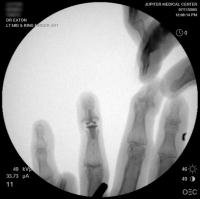

Intraoperative fluoroscopy using the same technique as above. The trial spacers:

The final implant:

Xrays one year out.